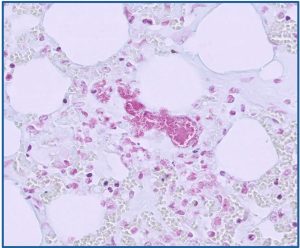

Kidney from a sheep with acorn toxicity. Tubules are often dilated and filled with eosinophilic fluid, haemorrhage, necrotic debris and degenerate neutrophils (arrows). There is also multifocal interstitial information (circle)